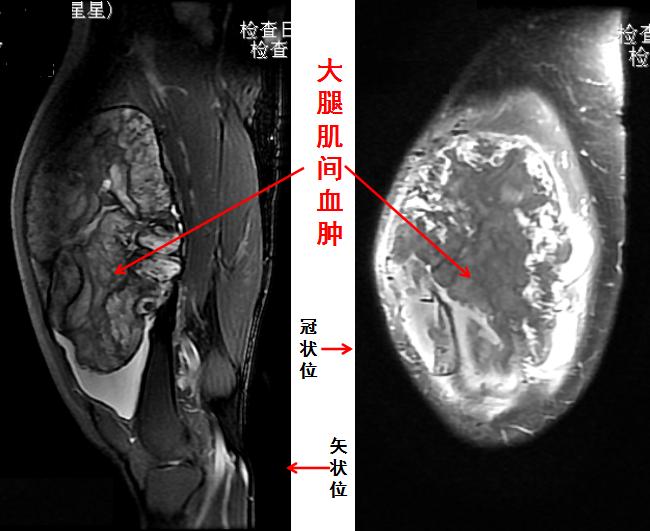

MRI检查示大腿肿块为肌间慢性血肿

一般来说,首选X线摄片检查是基本次序,因为它对骨性病变的观察比较满意,而且整体观最佳。CT检查能提供更为清晰的骨质结构细节,诊断符合率更高,往往是作为X线摄片仍难以诊断时的后续手段。而MRI检查,最适于关节及软组织病变的观察,如果临床诊断指向这些部位,就可直接选择MRI检查,更为准确快捷。